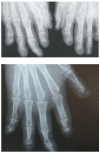

Sarcoidosis is a multisystem inflammatory disorder of unknown cause. It most commonly affects the pulmonary system but can also affect the musculoskeletal system, albeit less frequently. In patients with sarcoidosis, rheumatic involvement is polymorphic. It can be the presenting symptom of the disease or can appear during its progression. Articular involvement is dominated by nonspecific arthralgia, polyarthritis, and Löfgren's syndrome, which is defined as the presence of lung adenopathy, arthralgia (or arthritis), and erythema nodosum. Skeletal manifestations, especially dactylitis, appear mainly as complications of chronic, multiorgan sarcoidosis. Muscle involvement in sarcoidosis is rare and usually asymptomatic. The diagnosis of rheumatic sarcoidosis is based on X-ray findings and magnetic resonance imaging findings, although the definitive diagnosis is made by anatomopathological study of biopsy samples. Musculoskeletal involvement in sarcoidosis is generally relieved with nonsteroidal anti-inflammatory drugs or corticosteroids. In corticosteroid-resistant or -dependent forms of the disease, immunosuppressive therapy, such as treatment with methotrexate or anti-TNF-α, is employed. The aim of this review was to present an overview of the various types of osteoarticular and muscle involvement in sarcoidosis, focusing on their diagnosis and management.